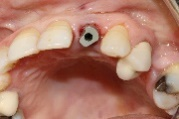

After implant placement (Figure 9), the primary stability of the implant was satisfactory (greater than 35N), the provisional abutment was fixed (Figure 10) and a post-operative retroalveolar radiograph was taken for radiological control of the implant and adaptation of the provisional abutment (Figure 11).

Figure 10. Fixing the temporary abutment to the implant